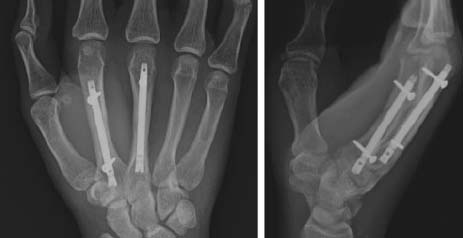

(a) 銃撃による第5中手骨骨幹部の粉砕骨折の術前X線写真。 (b) 非観血的整復および経皮的ピンニング後の術中透視像、および(c, d) 術後3週および23週のX線写真。骨折の癒合が進行し、骨のアライメントも良好である。

中手骨骨幹部骨折

中手骨骨幹部骨折は、中手骨間靭帯の支持により、しばしば安定します。骨幹部骨折のパターンは、多くの場合、横骨折、斜骨折(螺旋骨折を含む)、粉砕骨折です。骨幹部骨折治癒過程では、不完全癒合による骨の短縮・角度、回旋が問題となります。変形が進むにつれて握力の低下が顕著な特徴となります。中手骨が1ミリメートル短縮する事により、握力が6.5%失われることが示されています。中手骨骨幹部骨折で許容される骨折角度は、第2指と3指で10°未満、第4指で20°未満、第5指で30°未満です。また、わずか5°の回旋異常でも1.5cmの指の重なりが生じることが示されています。指はすべて舟状骨結節の方向を指すべきです。回旋変形がある場合、指はハサミに見えるように見えます。骨幹部骨折の大部分は、徒手整復の有無にかかわらず、非手術的に治療できます。第5指中手骨幹骨折の患者139名を追跡した研究では、角度が30°を超える患者では、手術治療と保存治療で骨の強度、握力、美観スコアに統計的に有意な差は見られませんでした。非観血的整復でアライメントは良好でも整復の維持が困難な症例では、経皮的ピン固定が必要となることがあります。ピン固定には、クロスピン、IMピン、横断ピンなど、複数の中手骨頭にまたがって長さを維持できる様々な方法があります。非観血的整復を試みた後に整復不能な骨折がある場合、しばしば観血的整復が必要となります。また、開放骨折、多発骨折、ピン固定では安定性が得られない骨折にも適応となります。観血的整復は、経皮的ピン固定または内固定と併用することができます。内固定法の選択肢としては、髄内スクリュー、骨片間スクリュー、プレート&スクリューなどがあります。